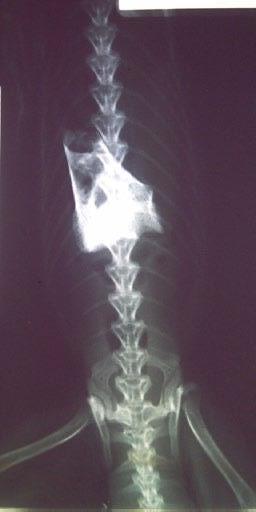

Cha Cha is a 9-month-old male neutered Domestic Shorthair cat. He was initially seen by another clinic for straining to defecate and blood in the stool. He was otherwise very bright, active, eating well and in good body condition.

An ultrasound at the other clinic identified marked thickening of the descending colon.

The owners were advised that this was most likely to be neoplastic and were advised to undertake a subtotal colectomy.

The owners came to us for a second opinion. Our ultrasound confirmed the findings of the previous clinic. There was a marked focal thickening of the descending colon:

Figure 2. Ultrasound image of the caudal abdomen showing marked thickening (10.9 mm) of the descending colon

Although neoplasia was indeed considered in the differential diagnosis, a recent publication (Müller et al JFMS 2023—Abdominal ultrasonographic findings of cats with feline infectious peritonitis—an update) had also indicated that this was amongst the increasingly varied recognised presentations for FIP. Indeed, historically it was referred to as ‘focal FIP’.

A repeat ultrasound after 10 days of treatment indicated early evidence of a reduction of the colonic lesion.

We planned to provide 42 days of treatment and serially assess the lesion by ultrasound to determine the effect of the treatment.

Here are the sequential images:

At the time of writing, 1 month after completion of a 42 day course of medication, Cha Cha is asymptomatic, with no clinical, clinical pathological, or sonographically detectable signs of disease. This response is very difficult to attribute to anything other than highly effective treatment of focal, colonic ‘dry’ FIP with GS-441524.